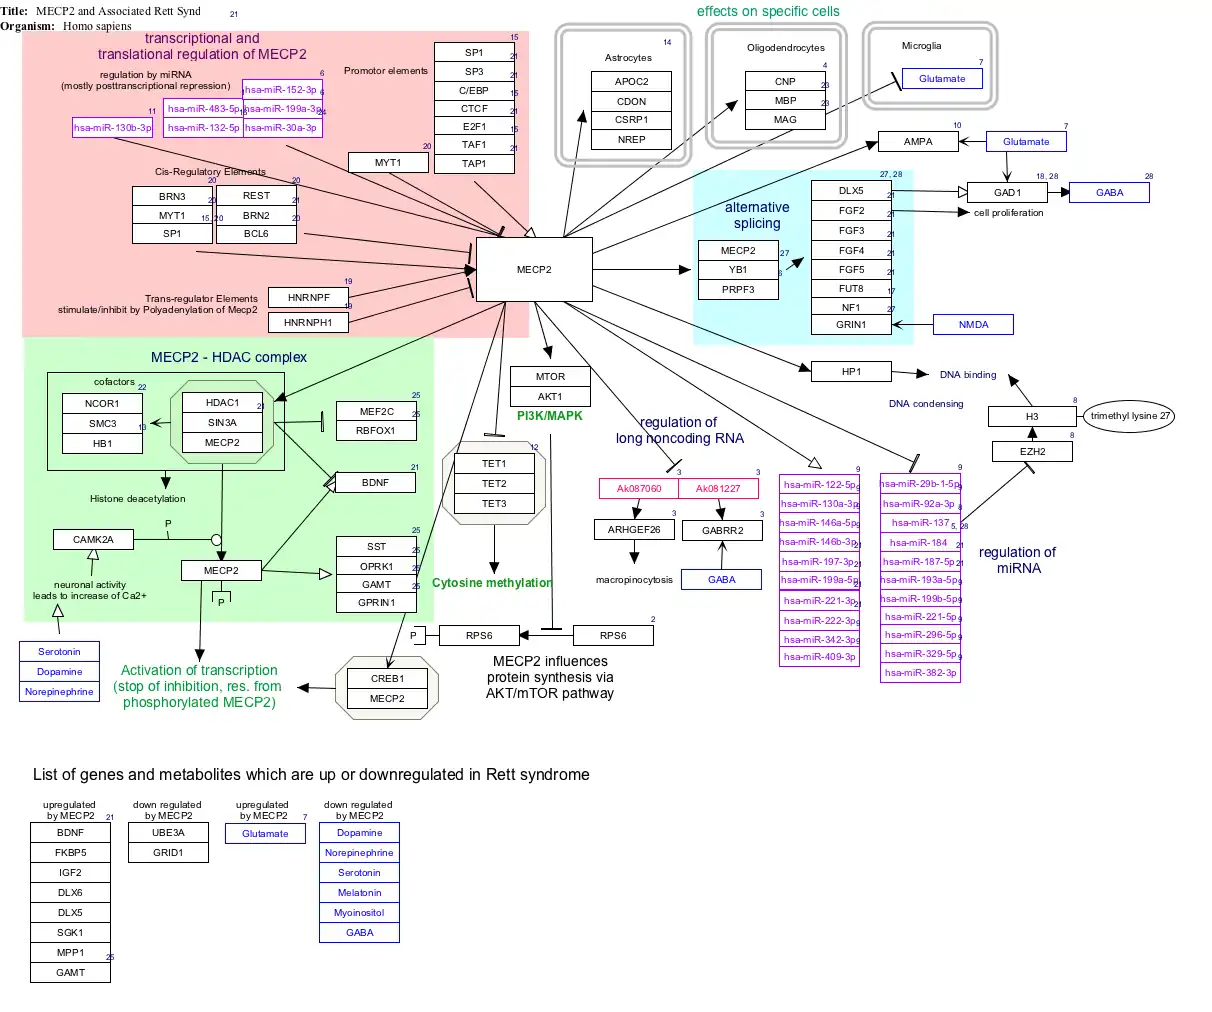

Interactive pathway map

Click on genes, proteins and metabolites below to visit related articles. [§ 1]